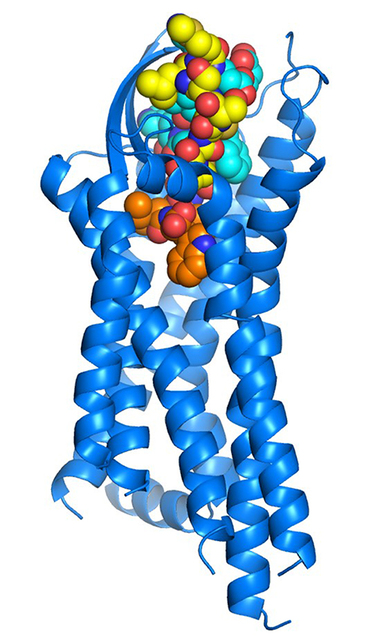

土井知子准教授らの研究グループは、血液循環において局所的な血流の調節を行う血管収縮因子エンドセリンと結合したエンドセリンB型受容体の構造を、結合していない状態と合わせて解明しました。これらを基盤とする新たな薬剤の開発が期待されます。

血管収縮因子エンドセリンの受容体初期活性化機構を解明

土井知子准教授らの研究グループは、血液循環において局所的な血流の調節を行う血管収縮因子エンドセリンと結合したエンドセリンB型受容体の構造を、結合していない状態と合わせて解明しました。これらを基盤とする新たな薬剤の開発が期待されます。 第4回花山天文台野外コンサート